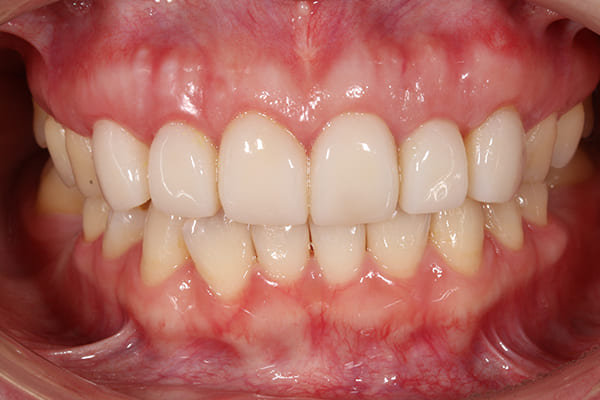

こちらが最終補綴物を装着した後の口腔内写真です。

初診時に見られた歯肉の炎症は改善し、健康的で引き締まった歯肉へと回復しています。

補綴物も高い透明感と自然な質感を備えており、審美性・機能性ともに理想的な仕上がりとなりました。

健康的で引き締まった歯肉へと回復しています。補綴物も高い透明感と自然な質感を備えており、審美性・機能性ともに理想的な仕上がりとなりました。